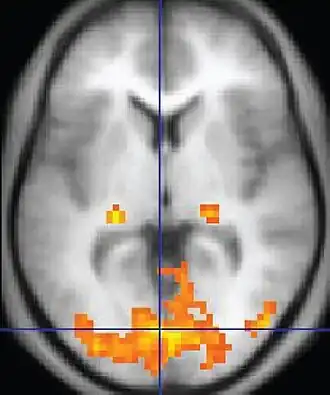

In modern neuroscience, neuroimaging techniques are of particular importance as the main research methods of neuroscientists. Functional magnetic resonance imaging (fMRI) measures changes in the magnetic field of the brain associated with blood flow. Areas of increased blood flow indicate that the corresponding brain region is particularly active. Positron emission tomography (PET) uses radioactive substances to detect a range of metabolic changes in the brain. Electroencephalography (EEG) measures the electrical activity of the brain, usually by placing electrodes on the scalp and measuring the voltage differences between them. These techniques are often employed to measure brain changes under particular circumstances, for example, while engaged in a specific cognitive task. Important insights are also gained from patients and laboratory animals with brain damage, helping neuroscientists understand the function of the damaged area and how its absence affects the remaining brain.[165]